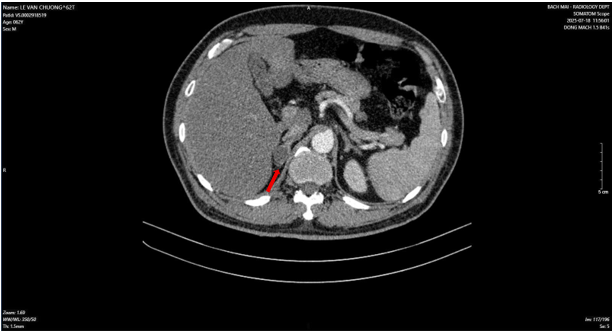

Sau đó, bệnh nhân được bổ sung các xét nghiệm đánh giá toàn thân. Kết quả phim chụp cắt lớp vi tính ngực và bụng cho thấy, không chỉ có khối u ở tuyến tiền liệt mà bệnh nhân còn có nhiều khối u khác ở phổi (Hình 2), tuyến thượng thận (Hình 3) và xương (Hình 4).

Hình 2: Hình ảnh 02 khối u bờ đa cung ở nhu mô thùy giữa phổi phải, dính vào màng phổi trung thất (mũi tên đỏ) kèm nhiều nốt đặc nhỏ rải rác nhu mô phổi hai bên (mũi tên vàng) gợi ý tổn thương thứ phát.

Hình 3: Hình ảnh dày tuyến thượng thận phải tạo nốt có kích thước 19 x 17 mm (mũi tên đỏ).